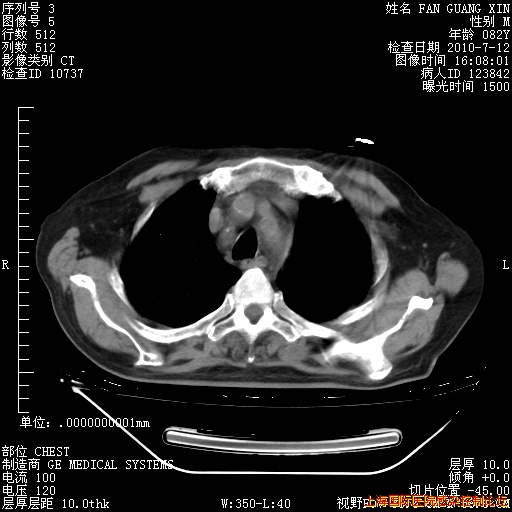

今天复查CT

今天CT

整整相隔30天的肺部CT好像有所好转啊。甲强龙减量第3天,需要观察体温。